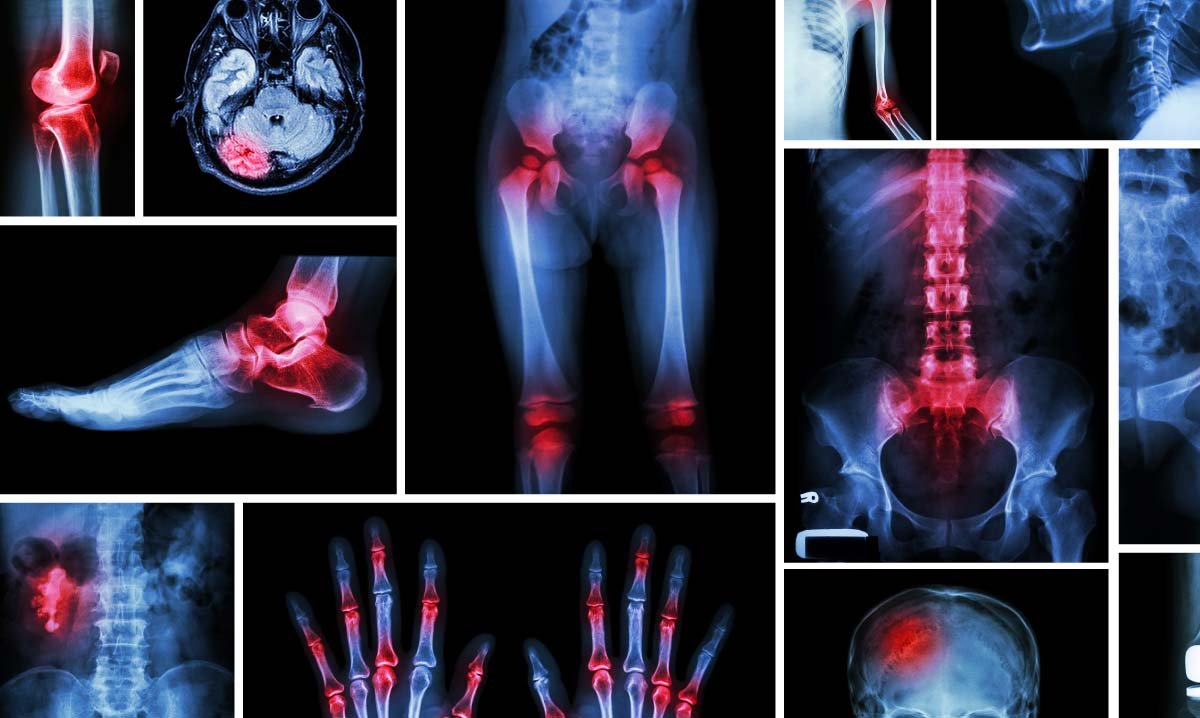

Orthopedic services in San Diego focus on the diagnosis, treatment, rehabilitation, and prevention of disorders affecting the bones, joints, muscles, ligaments, and tendons. The musculoskeletal system plays a vital role in movement, strength, and stability. At Grossmont Endoscopy Institute, our orthopedic specialists provide expert care for a wide range of conditions — from minor injuries to complex bone and joint disorders.

Accurate diagnosis is the first step toward restoring mobility and relieving pain. To determine the cause of your symptoms, your orthopedic physician will review your medical history and perform a physical examination. Additional diagnostic tests may include:

- X-rays to evaluate bones and joints

- MRI and CT scans for soft tissue and ligament injuries